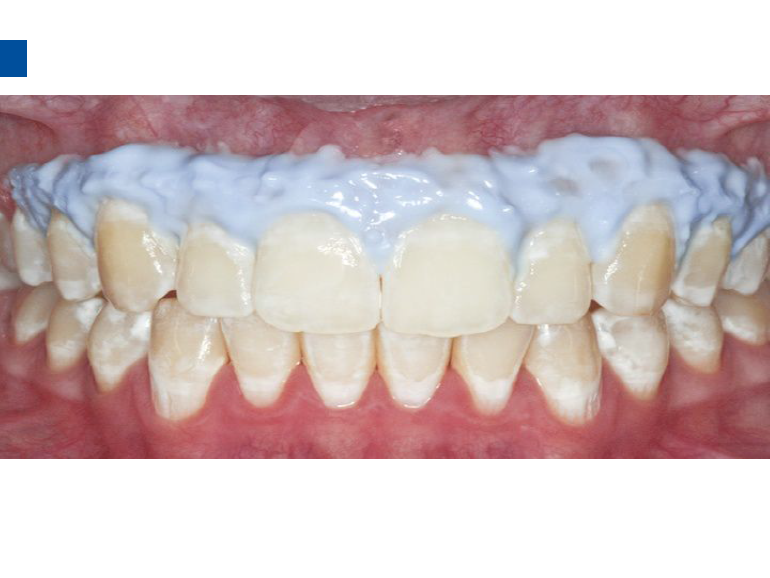

二、爱康渗透树脂唇颊面装Icon Caries Infiltrant – vestibular,治疗唇颊面釉质早期龋。(整个套装包含一次治疗两至三个早期龋损所需的材料。一次性使用,如果邻牙有类似病变可一并治疗)。

1、治疗之前清洁患牙及邻牙,冲洗干净,上橡皮障。避免使用如Flexi Dam之类的热塑性橡胶材质的橡皮障。放置合适的楔子进入牙间隙,将柄部弯曲或折断可以让楔子更好的进入邻面。

2、将配套唇颊面龋损治疗的注射头装在含有爱康酸蚀剂Icon-Etch的注射器之上。

3、小心旋转注射器柄部,将足量材料涂布于龋损区域之上,等待2分钟,并用棉球去除多余材料,酸蚀范围应至龋损外2mm处,如果正畸患者托槽取下后发现牙面大范围早期龋损则需酸蚀整个牙面。(单手可完成注射器操作)。